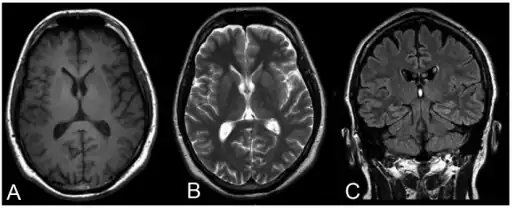

Progressive myoclonic epilepsy type 1-a,b) MRI c) FLAIR | |